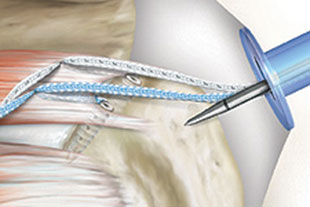

Ablauf einer beispielhaften Naht der Rotatorenmanschette

Einbringen eines Fadenankers in den Oberarmkopf

Versenken des Fadenankers unter der Knochenoberfläche

Einbringen des am Anker befestigten Fadens in die Sehne

Einbringen eines 2. Fadenankers und eines 2. Fadens in die Sehne

Zug der Sehnenplatte über die eingebrachten Fäden zum ursprünglichen Ansatzpunkt der Sehne

Einbringen eines weiteren Ankers zur Fixierung der Fäden und somit der Sehnenplatte am ursprünglichen Ansatzpunkt

Einbringen eines 4. Ankers und Fixierung der überkreuzten Fäden zur optimalen Stabilisierung der Rotatorenmanschette am Oberarmknochen

Alle Bilder der Rotatorenmanschettennaht mit freundlicher Genehmigung der Firma Arthrex®